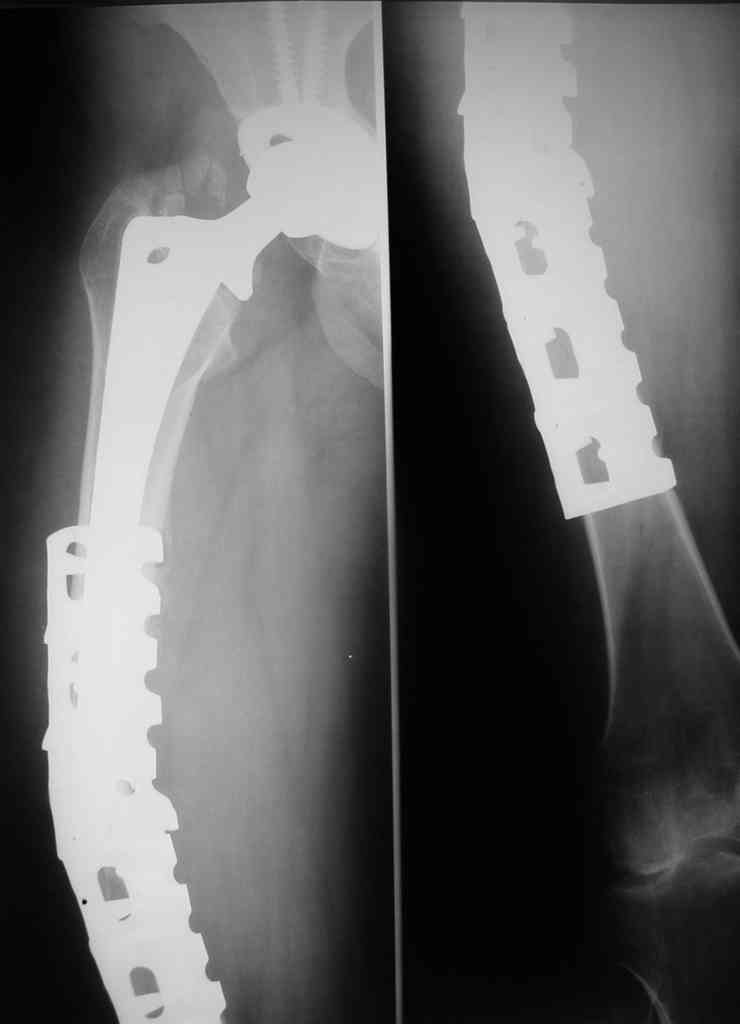

В июне 2006 года в ДТП была сбита автомобилем и получила поперечный оскольчатый околопротезный перелом в с/з диафиза бедра, с сохранением стабильности ножки протеза. Через 2 недели после травмы в клинике был произведен открытый остеосинтез бедра пластиной Bridge Plate DePuy. Больная ходила с костылями, через 3 месяца после остеосинтеза начала постепенно увеличивать нагрузку на ногу.

Через 6 месяцев клинически и на контрольных рентгенограммах было выявлена деформация бедра. Планируется провести реостеосинтез бедра аналогичной пластиной большей длины с применением костной аутопластики и (или) материалов типа MIIG, IGNITE, ALLOMATRIX.